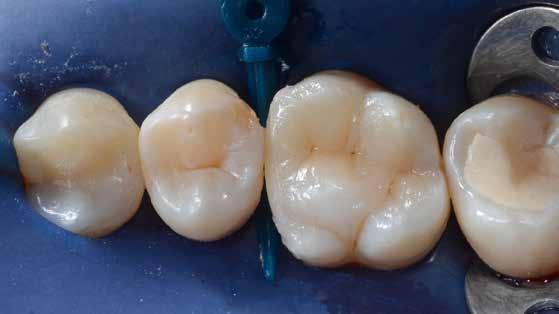

14. ábra: Egy moláris fog preoperatív állapota.

15. ábra: Egy moláris fog postoperatív fotója.